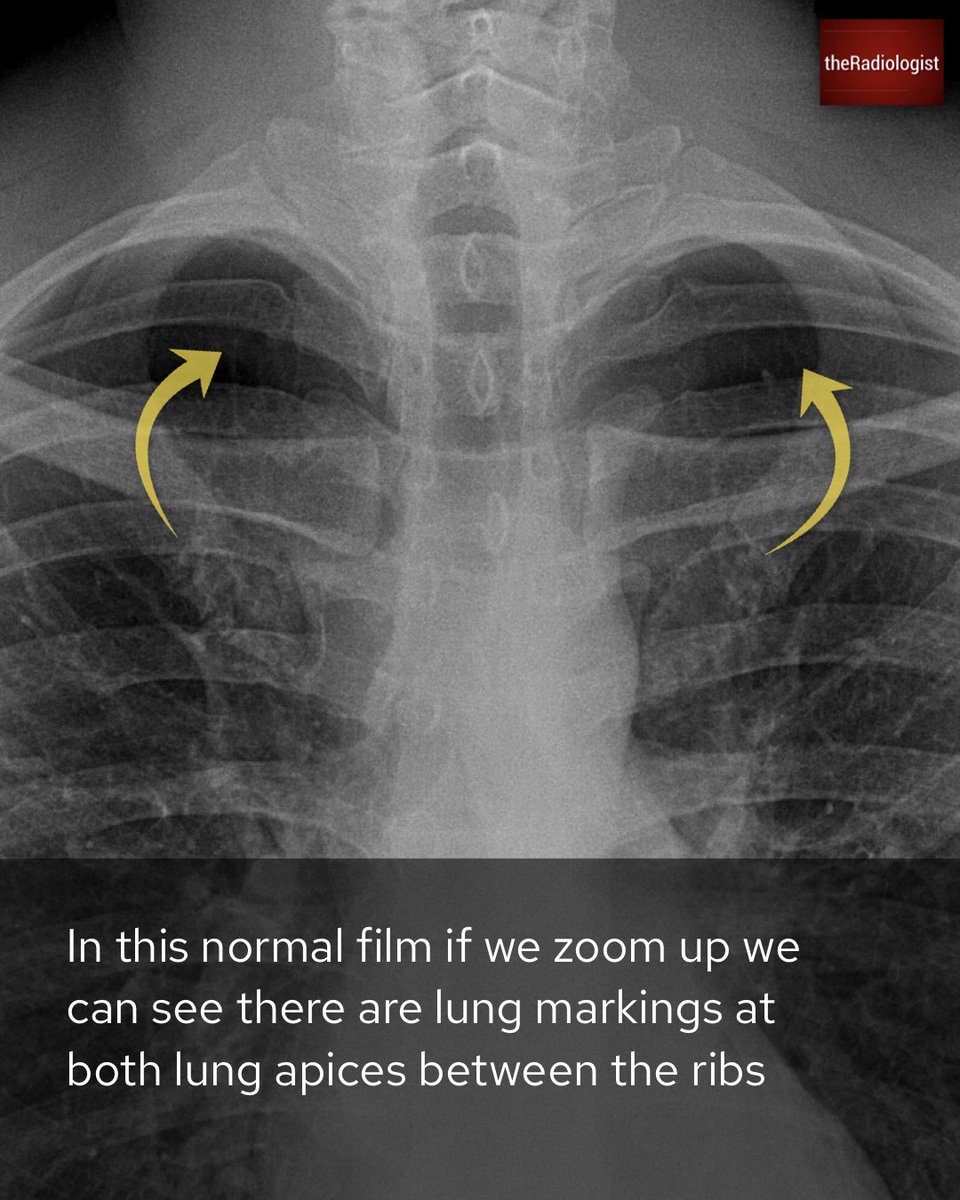

Explanation 3/3

Explanation 2/3

Explanation 1/3